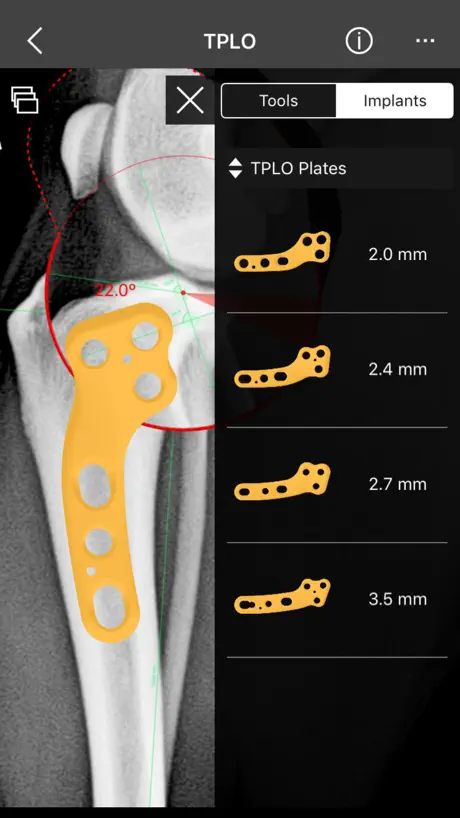

This is a useful tool for traumatology and orthopaedic surgical planning veterinary, including advanced techniques for treat canine anterior cruciate ligament (ACL) injuries (TPLO and CTWO).

f) Circular cut, TPLO.

4. Catalogue of BETA Implants locking plates, in 2.0, 2.4, 2.7 and 3.5 sizes:

m) TPLO plates

This is a useful tool for traumatology and orthopaedic surgical planning veterinary, including advanced techniques for treat canine anterior cruciate ligament (ACL) injuries (TPLO and CTWO).

f) Circular cut, TPLO.

4. Catalogue of BETA Implants locking plates, in 2.0, 2.4, 2.7 and 3.5 sizes:

m) TPLO plates